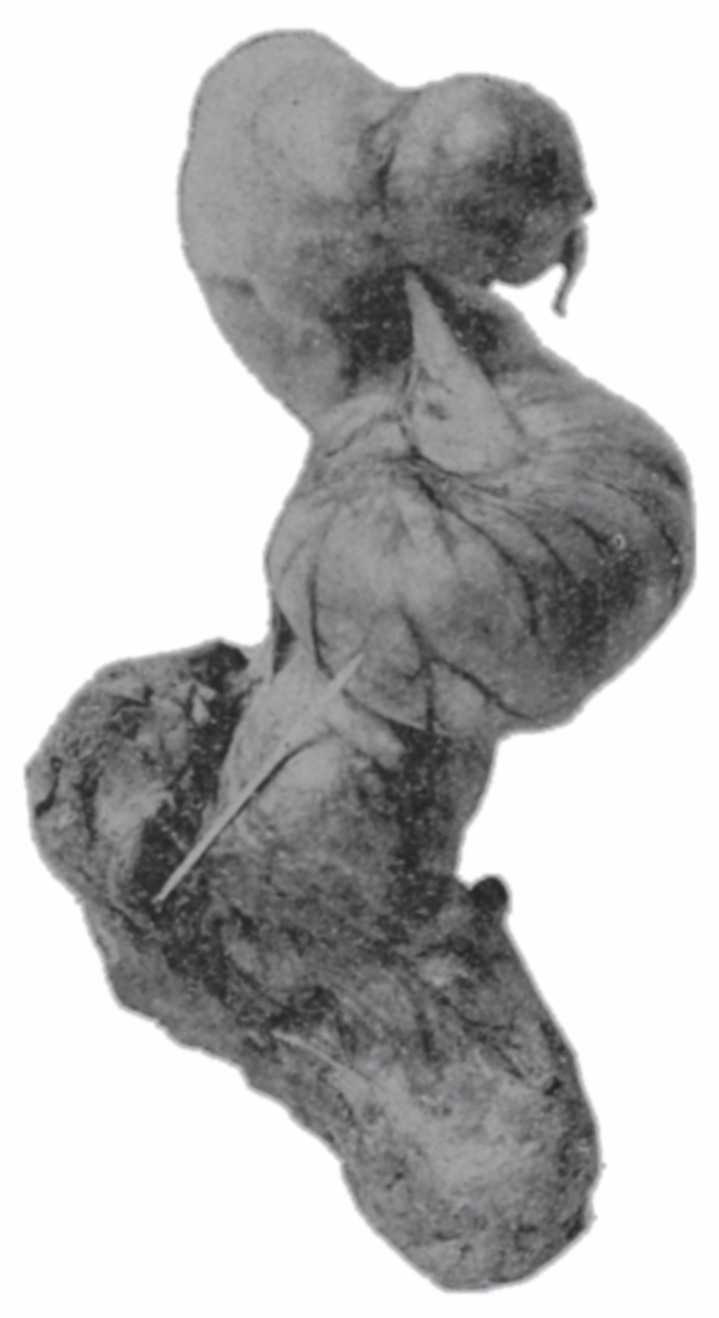

The photographic reproductions here published are documentary evidence of the existence of the obstructions under discussion. The sketch, Fig. 33, which was drawn from the valve while under the microscopic lens, exhibits the character of these obstructions and proves it that of a typic anatomic valve, and the absence of permanent bands of any other character in this organ is evidence that the semilunar valves and the so-called plica transversalis recti, Falten des Rectums, sphincter ani tertius, superior sphincter, and detrusor fecium muscles are one and the same thing and this thing is essentially a valve. It is most prominent when the gut is most distended.

The rectum may present to the eye of the imaginative observer the appearance of a chain of urinary bladders, communicating one with another by means of irregularly elliptic openings set at varying axes, and bounded by the nonparallel borders of the rectal valves. In the normal rectum the air-pressure smooths the mucous membrane evenly over the entire surface of the gut, as may be observed in the photographic illustrations. The normal mucous membrane of the so-called ampulla appears at first wet and of a shining bluish gray. As it dries, under the influence of gravitation the blue venous tint fades out of the gray and the wall assumes a pink tint.[39] Presently it acquires the appearance of parchment, and sometimes it appears painted at rare intervals with ramifying little arteries which may be crowded and overlapped by the larger companion veins; the latter are less arborescent and more suddenly dive and disappear in the bowel-wall. In time, over all there comes a sheen and the vascular pictures may fade away. These phenomena appear exactly as described only in the healthy rectum. In the diseased organ the color varies much.